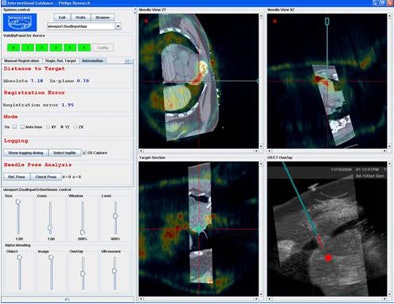

Krücker and his colleagues built and tested a prototype interventional navigation system to evaluate electromagnetic tracking during soft-tissue ablation and biopsies.

The system was based on the 2005 Aurora "square" tracking system (NDI) along with several additions, including custom Philips software that enabled tracking of a needle, an ultrasound probe (iU22 scanner, Philips Medical Systems, Andover, MA), and up to eight respiratory motion sensors relative to 3D images (Traxtal). The system supports manual registration and simultaneous display of two 3D images.

An electromagnetic tracking sensor was attached to the ultrasound probe and guided by customized stylus/sheath combinations and tracked radiofrequency ablation needle guides with integrated miniaturized sensor coils in the needle tip (Traxtal). The accuracy of needle tracking was compared with the needle position at CT.

"For analysis we compared the confirmed position with the fiducials with several confirmation CT scans," he said. Also, targets were compared based on conventional ultrasound or 16-detector-row CT guidance (Brilliance, Philips Medical Systems).

The tracking analysis was performed on 18 patients (13 men, 5 women; mean age 58.4 ± 12.9 years) in order to perform 11 radiofrequency ablations and seven biopsies in target sites that included the liver (11), kidney (3), lung (2), neck (1), and above the heart (1).

"A nice example of why tracking is so attractive for these procedures is because needles can and do bend," Krücker said. Calculating needle position based on the insertion angle can result in significant errors, and the study results included needle angle insertion tracking in six of the patients compared to conventional image guidance.

"The procedures were all clinically successful; we had a total of 41 confirmed needle positions in those 18 patients (one to four per patient)," Krücker said. "The average fiducial registration error was 1.5 mm, and the additional setup time, the steps that were necessary for the procedure compared to conventional workflow, was about six and a quarter minutes using the passive fiducials only."

Compared to traditional CT or ultrasound guidance, the average tracking accuracy of the system was 3.8 mm when using only external skin fiducials for registration, improving to an average of 2.9 mm when an internal needle position was also used for registration.